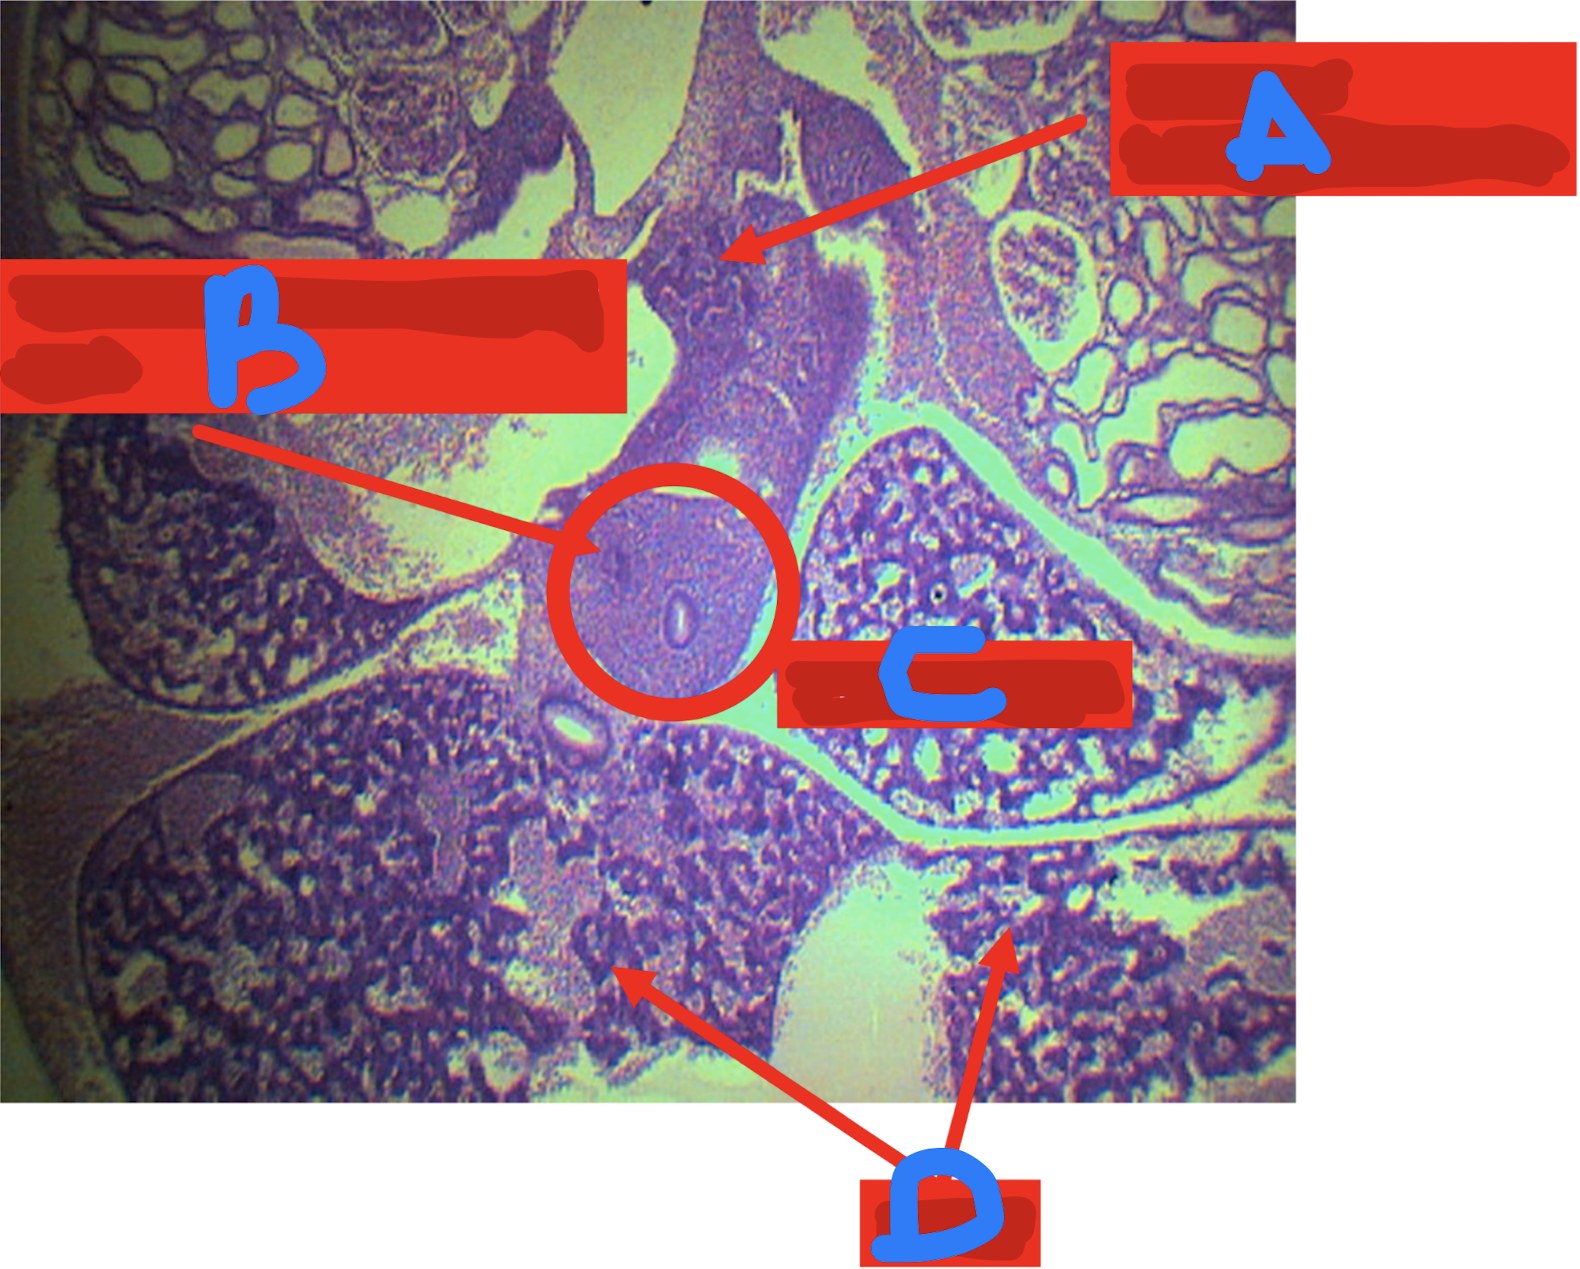

A: cloaca

B: urorectal septum

C: urogenital canal/sinus

D: anal canal (anorectal canal)

Identify the structure